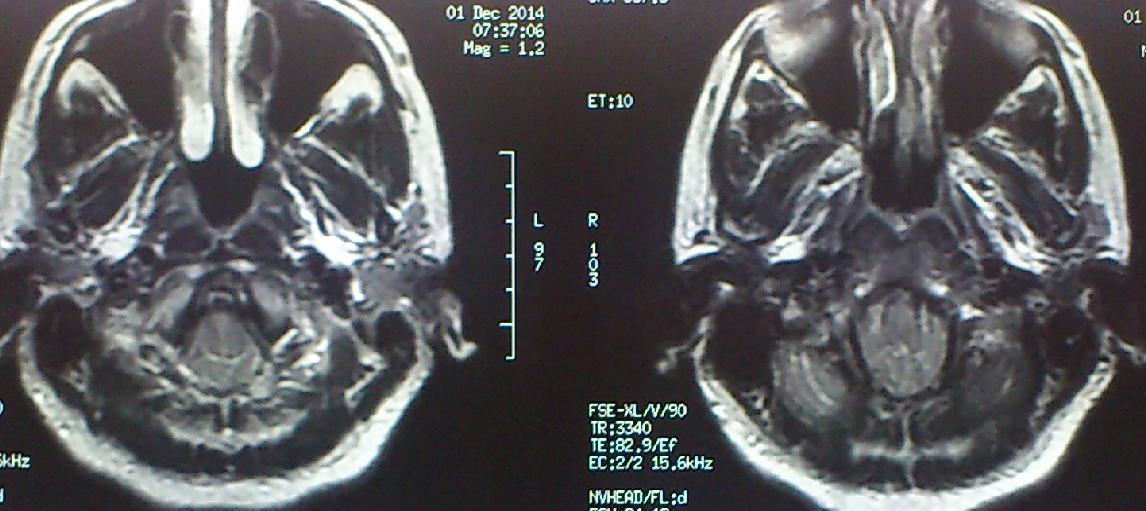

Ασθενής  γυναίκα 49 ετών προσήλθε λόγω υπινιακής κεφαλαλγίας εκλυόμενης και επιδεινούμενης  κατά την επίκυψη και  την άρση βάρους  ( Valsalva maneuvers ) με συνοδό αίσθημα αιμωδιών  άνω και κάτω άκρων. Ο προεγχειρητικός έλεγχος με μαγνητική τομογραφία  του κρανιοσπονδυλικού άξονα ανέδειξε εικόνα συμβατή με Chiari τύπου I : κατάσπαση των παρεγκεφαλιδικών αμυγδαλών 8 mm με κατάληψη- συμφόρηση του ινιακού τρήματος και συνοδό συριγγομυελία καθ’ όλο το μήκος του αυχενοθωρακικου μυελού. Η ασθενής υποβλήθηκε σε υπινιακή κρανιοτομία, αφαίρεση του οπίσθιου τόξου του άτλαντα (Α1) και εκτομή των παρεγκεφαλιδικών αμυγδαλών αποκαθιστώντας την υδροδυναμική του εγκεφαλονωτιαίου υγρού. Πραγματοποιήθηκε πλαστική σκληράς μήνιγγος και δεν επανατοποθετήθηκε ο οστικός κρημνός. Η ασθενής μετεγχειρητικά παρουσίασε  πλήρη ύφεση της κεφαλαλγίας και σταδιακή αποκατάσταση των αιμωδιών. Ο μετεγχειρητικός απεικονιστικός έλεγχος ανέδειξε την αποσυμπίεση στο επίπεδο της κρανιοσπονδυλικής συμβολής και σαφή μείωση των διαστάσεων της συριγγομυελίας.

Προεγχειρητικός απεικονιστικός έλεγχος